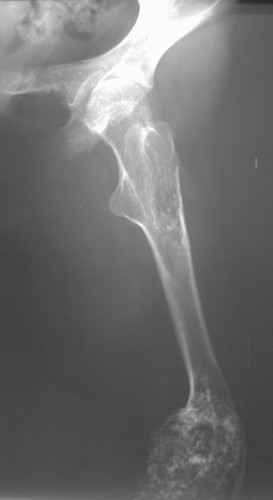

Диагноз: Дисхондроплазия. Варусная деформация дистального метафиза правой бедренной кости; состояние после оперативных вмешательств (1993 и1994 гг.).

Деформация правой нижней конечности с 6 месяцев (стала прогрессировать после года, с момента начала ходьбы). Поставлен диагноз болезнь Олье, варусная деформация, укорочение правой нижней конечности на 4,5 см. 1993 г. - операция остеоклазия на уровне очагов поражения в н/3 правой бедренной кости и в/3 правой большеберцовой кости с одномоментной коррекцией деформации и фиксацией костных фрагментов спицами Киршнера.После начала статической нагрузки (1994 г.) появился рецидив деформации и укорочения. Вторая операция - ЧКО АВФ, аппарат демонтирован через 2недели в связи с развившимся на уровне стержня переломом, после чего находилась в гипсовой повязке до консолидации костных фрагментов. Далеелечилась консервативно в гипсовой повязке. Выраженная деформация и укорочение правой нижней конечности. Относительная длина бедер: справа -34 см, слева - 51 см; анатомическая длина голеней: справа - 29 см, слева - 39 см. Величина варусной деформации на уровне дистального отдела правого бедра составляет - 80 град. Амплитуда движений в коленных суставах (разгибание/сгибание ): справа - 0/0/100 град.; слева - 0/0/30 град. Отмечается боковая и ротационная нестабильность на уровне правого коленного сустава. Амплитуда движений в голеностопных суставах - в норме. Тактика лечения? Заранее благодарю! С уважением,А.В.Владзимирский

Высылаю вам фото подобной больной, у нее тоже первая попытка до меня была безуспешной.

Нужен аппарат Илизарова стабильный с множеством спиц с напайкой, временной фиксацией колена аппаратом на голени. Наверное, проще первый раз начать с бедра, остеотомию выполнить прямо на уровне перехода очага в дистальный метафиз бедра. Дистракционный остеогенез вызовет перестройку хрящевой ткани в костную. Понадобится еще пара этапов.